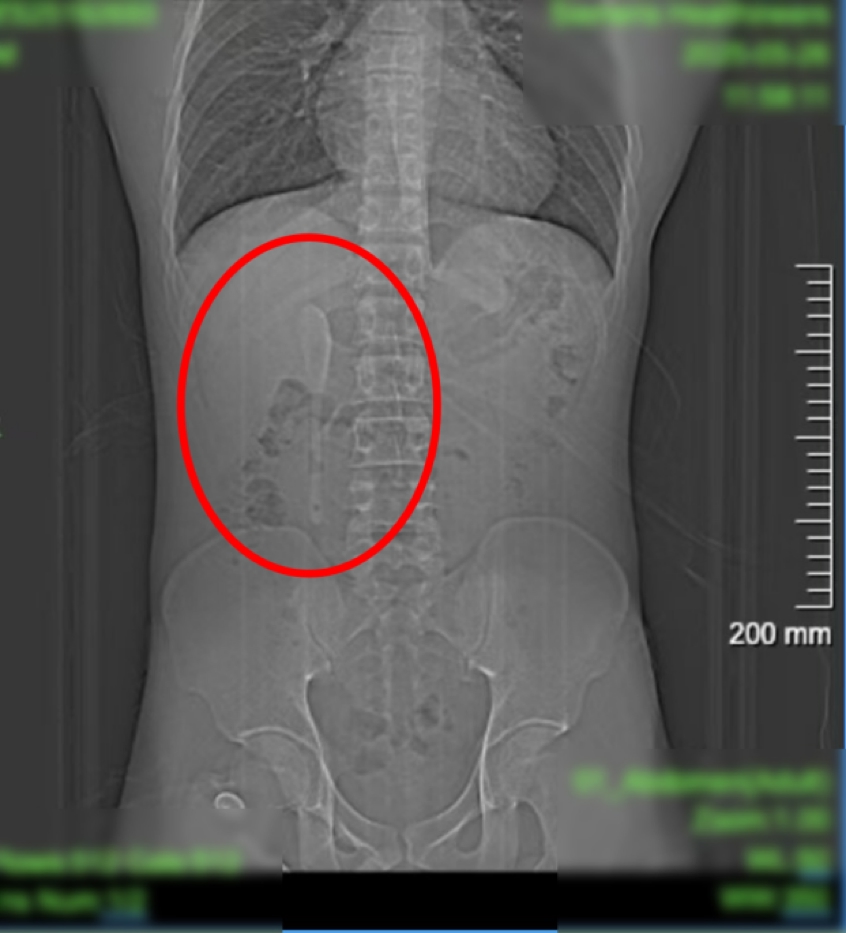

29岁的男子小言(化名),近期因外卖吃出塑料异物前往复旦大学附属中山医院急诊检查。谁知塑料没找到,竟意外发现腹中躺着一支近15厘米咖啡勺!CT显示这支近15厘米长勺状物体,严丝合缝地横亘于十二指肠球部与降部交界的生理狭窄处,稍有不慎即可能刺穿肠壁,引发腹膜炎或大出血。更离奇的是,身为严格自律的健身人士,小言对此毫无记忆,直至回溯半年前一场“梦境”般的经历……

这支被遗忘的勺子,历经6个月胃肠蠕动,最终精准卡进十二指肠球部与降部交界处。此处腔隙狭窄且肠壁极为菲薄,异物极易嵌顿,稍有不慎容易造成穿孔。中山医院内镜中心主任周平红教授解释:“勺子陶瓷质地光滑细长,十二指肠球降交界又是人体上消化道的生理狭窄处,内镜下取出难度极大。若失败,只能开腹手术。”

6月18日下午,小言被推进了内镜手术室。虽然团队对手术难度有所预判,但内镜画面仍让团队倒吸凉气——勺子的“头”卡在十二指肠球部,而它的“长柄”则一路延伸下去,拐了个弯卡在了更深的十二指肠降部与水平部交界处。